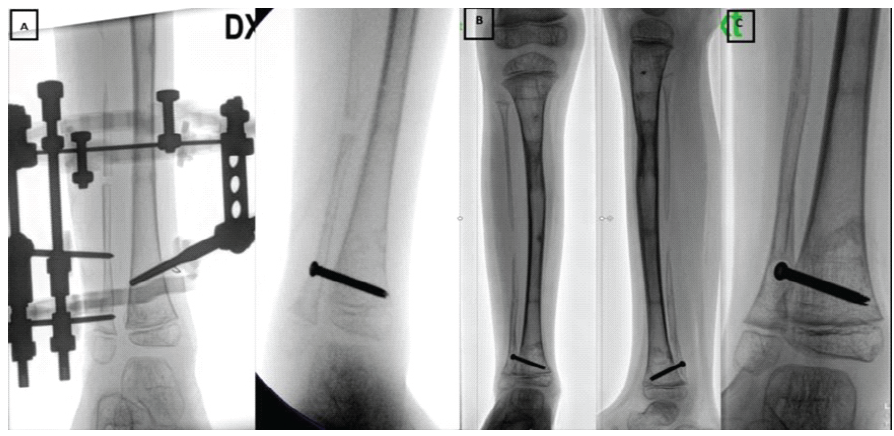

Four weeks later, the external fixator and K-wires were removed, and a long-leg cast was applied. During the subsequent 5 weeks of immobilization, the patient developed a progressive valgus deformity of the operated lower limb (Fig. 4c) and a proximal migration of the distal fibula suggesting instability at the distal tibiofibular joint. To address this, bone transport of the distal fibula (Fig. 5a) was performed. To maintain alignment, a distal positioning screw was inserted. However, the patient experienced recurrence of proximal fibular migration due to screw cut-out and fixation failure (Fig. 5b,c). Throughout the course of treatment, the contralateral limb with the PN remained skeletally unaffected.

Figure 5: (a) Bone lengthening of the right distal fibula (b) Proximal migration of the right distal fibula (c) Proximal fibular migration due to screw cut-out and fixation failure.